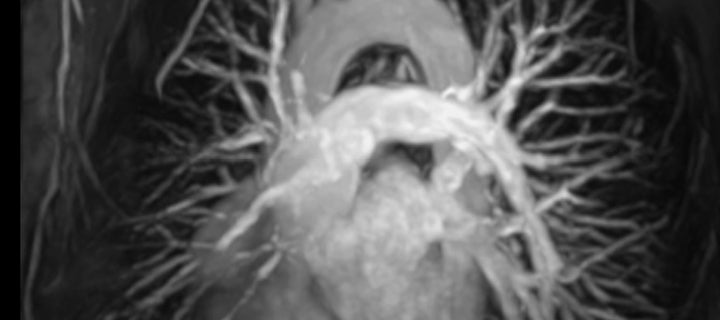

Cardiovascular magnetic resonance imaging, also known as cardiac MRI, is increasingly being used for non-invasive assessment of the function and structure of the cardiovascular system.

Cardiac MRI provides specific advantages over other cardiac imaging modalities when evaluating pathology in congenital heart disease, cardiac masses, cardiomyopathies, and in some aspects of ischaemic and valvular heart diseases. The strength of cardiac MRI in these pathologies includes its precise anatomical delineation of structures, characterisation of myocardial tissue, and accurate, reproducible measurements of blood volume and flow. Cardiac MRI is used in inpatient and outpatient settings, and is available primarily in major hospitals and some I-MED clinics.